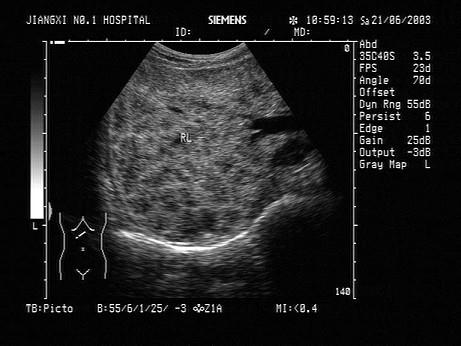

问题 男,60岁,胆囊结石病史多年,脾大小正常,有疫区接触史。结合超声声像图,诊断为?(?)

选项 A.肝血管瘤 B.血吸虫肝 C.肝癌 D.肝硬化 E.脂肪肝

答案 B